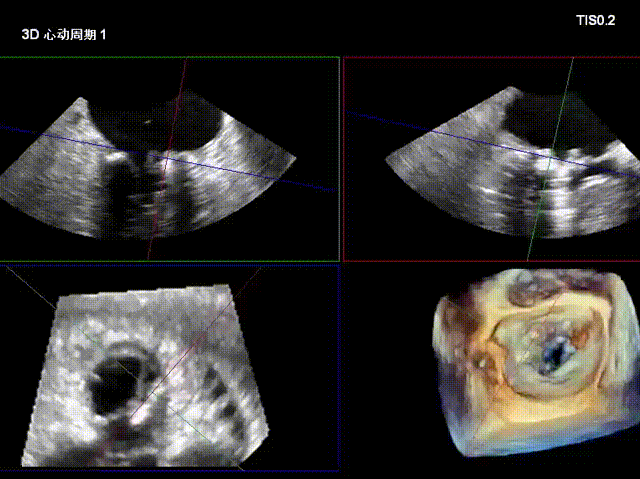

术后复查超声心动图显示:二尖瓣轻度返流,三尖瓣中度返流,二尖瓣可见金属夹回声,启闭正常;各心室大小正常,升主动脉不宽,主瓣回声增强,启闭良好;二尖瓣舒张期峰值流速1.4 m/s,功能面积2.1 cm²,跨瓣平均压差约4 mmHg。

术后心功能改善明显:LVdD 46mm,FS 33%,LA 45mm,LVDs 31mm,LVEF 62%。